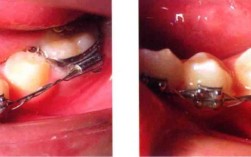

- 用钳子夹住这个远中末端,拉紧,使其紧贴托槽翼和弓丝,并与近中末端在托槽翼上方交叉,两个末端在托槽翼上方交叉,整体形状就像一个“8”字,弓丝被牢牢地固定在槽沟内。

(图片来源网络,侵删)- 用结扎丝钳将两个末端剪短(通常留2-3毫米)。

- 用结扎丝钳的尖端将末端向托槽翼方向弯折,使其紧贴托槽表面,避免刺伤口腔软组织(嘴唇、脸颊、牙龈),这是非常重要的安全步骤!